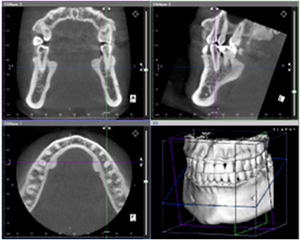

上顎のインプラント治療において行う骨の造成法です。

上顎には上顎洞という空洞があり、不用意に上顎洞を傷つけると術後上顎炎(蓄膿症)となってしまう

恐れがあります。こういった後遺症を防ぐために、骨造成が必要な場合があります。

当院では、上顎洞まで骨がなく骨造成が必要な場合、ソケットリフトという治療法を行っております。

若干切開を加え、歯肉を開いた後に上顎洞少し手前まで骨に穴を開け、骨の補填剤にて上顎洞を押し上げます。

患者さんへの負担も少なく、後述するサイナスリフト法より術後の腫れや痛みも少なくて済みます。

![]() |

|

| 術前CT | 術後CT |